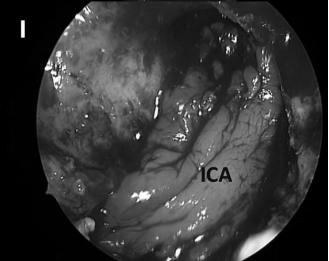

▼然后使用中鼻甲粘膜进行(图8I)进行闭合。

CD,斜坡凹陷;S,蝶鞍;SR,蝶嘴;T,肿瘤。

▼术后影像学证实了肿瘤全切(图7C)和颈静脉孔保留通畅(图7D)。在这种情况下,神经内镜筷子技术有助于顺利合适地暴露、探查神经和斜坡旁颈内动脉,并通过有限且定制的手术入路向下到达对侧肿瘤所在位置颈静脉孔区域。